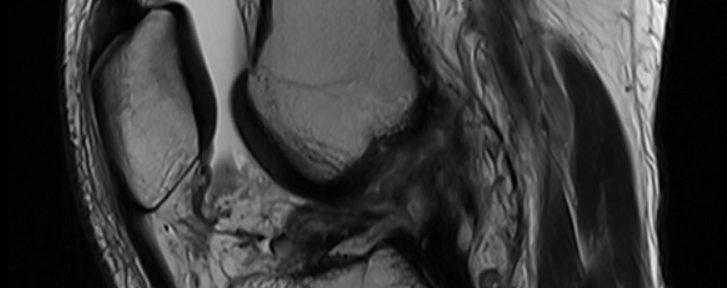

2022年6月11日、スケートボードのジャンプの着地に失敗し、右膝を捻った。6月25日にMRI撮影を行い、以下の診断を得た。

前十字靭帯断裂(断端が不明瞭(Iharaの分類Ⅳ))

2022年8月3日より、当院のナチュラリゼーション療法をオンラインにて開始した。オンライン治療と自宅でのナチュラリゼーションを継続し、治療開始から5ヶ月後に再度MRI撮影を行った。尚、患者は機能的装具を使用していなかった。

MRIの結果:

断裂した前十字靭帯は、太く緊張性のある形態で連続性を回復していた。(Iharaの治癒分類A)